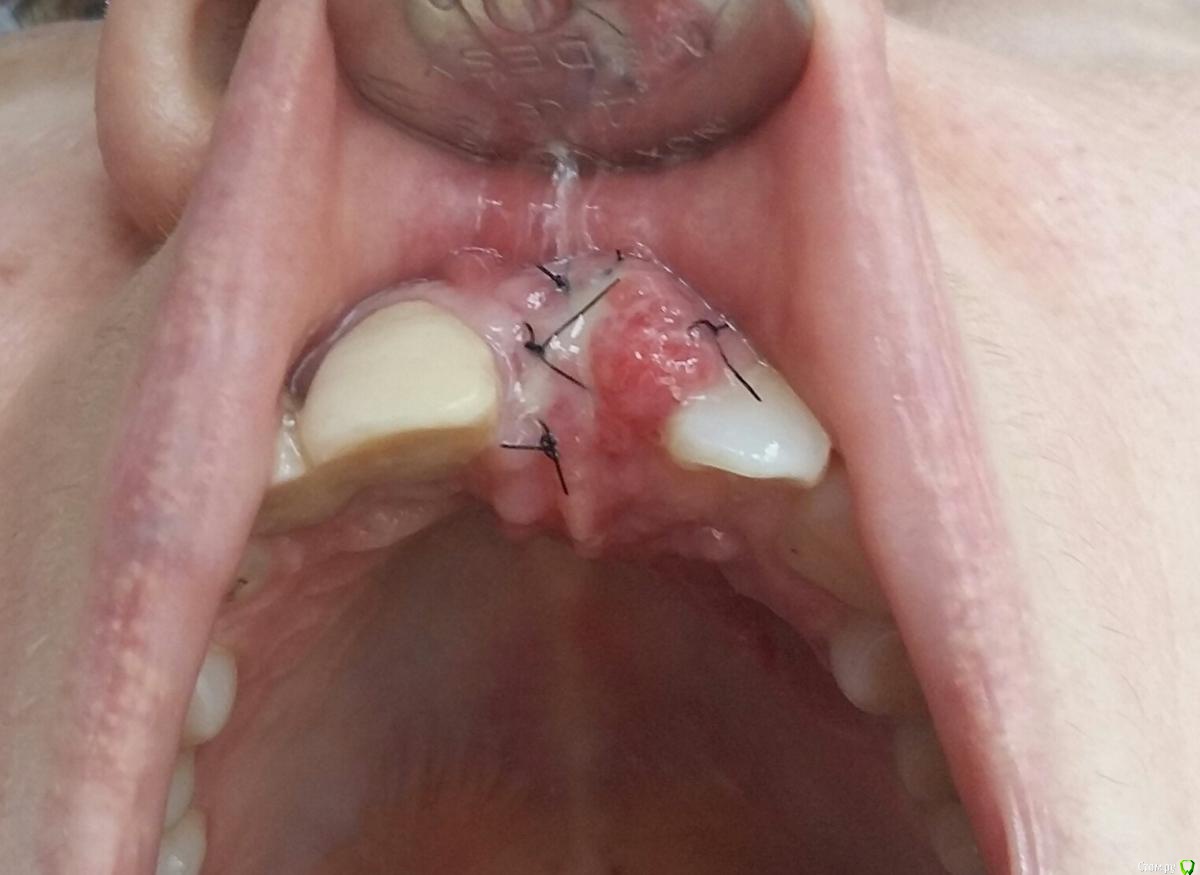

Kostoprav Опубликовано 8 ноября, 2017 Поделиться Опубликовано 8 ноября, 2017 заранее извиняюсь за качество фотографийдумал сделать все в один этап но торка ожидаемого не получил, поэтому пришлось накрыть винт випом.(материал osteobiol putyy) мне он очень понравиля ,удобный в работе. 17 Ссылка на комментарий

Kostoprav Опубликовано 8 ноября, 2017 Автор Поделиться Опубликовано 8 ноября, 2017 (изменено) putty перевод с английского как замазка, с випом больше шансов что он выживет поскольку есть питающая ножка, период наблюдения приблизительно год Изменено 8 ноября, 2017 пользователем Kostoprav Ссылка на комментарий